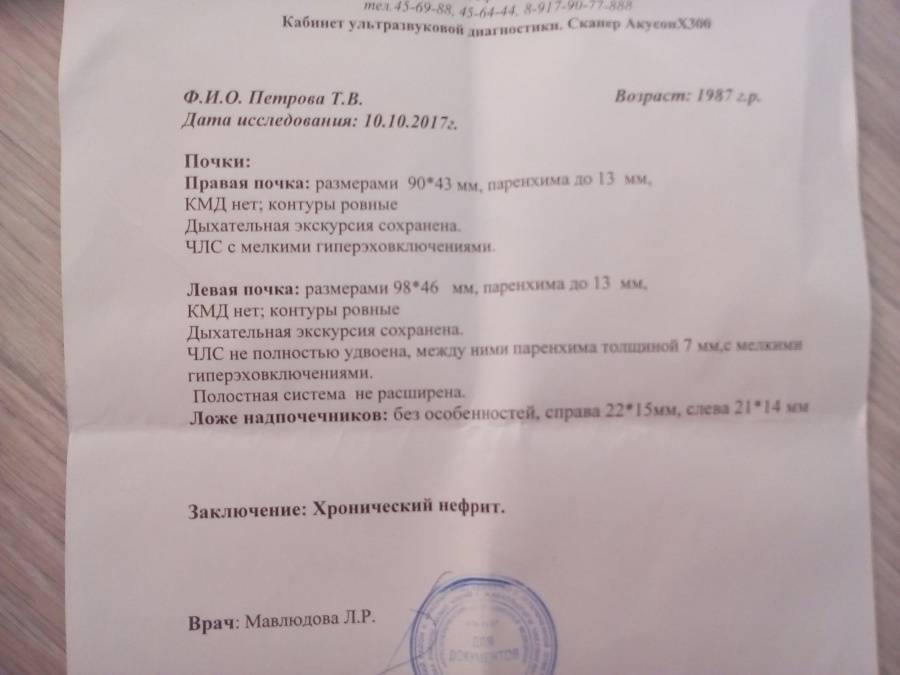

Раздел: Снимки-откровения